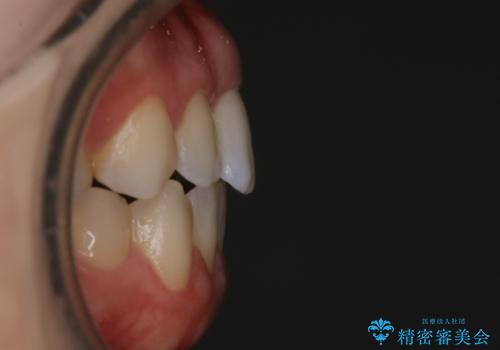

【非抜歯】上下の前歯が噛み合わないオープンバイトの治療

骨格的な問題もあり、噛んだ時に奥歯しか当たらず前歯の被蓋があまりない状態でした。

臼歯の位置が高く噛んだ時に奥歯しか当たらなかったり、舌癖などが原因で前歯が前に倒れてしまうことで上下の前歯の被蓋がなくなってしまっている状態をオープンバイトといいます。